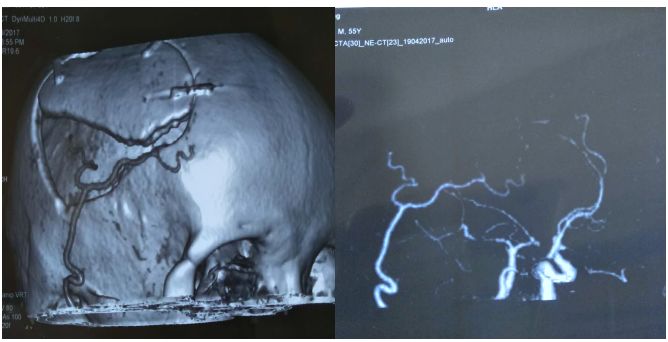

术前CTA

术后一周复查CTA 提示吻合口通畅

2018.05.30入院复查CTA:见双侧颞浅动脉均与颅内沟通